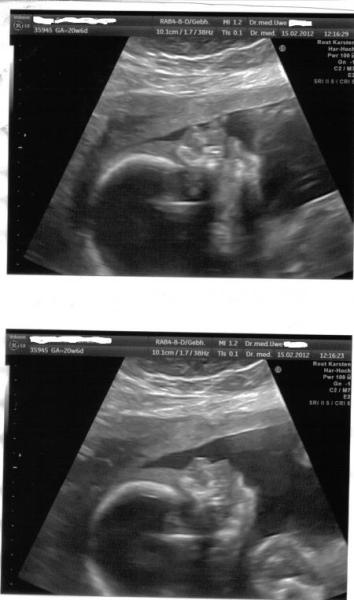

mit meinem baby ist alle top in ordnung. der schniepel der da ist der ist und bleibt auch also bekommen wir jetzt zu 100 % einen . Er hat am daum gelutscht und fruchtwasser getrunken. der arzt wollte 3 D machen aber Mister wollte sich nicht zeigen da war/bin ich ein wenig traurig So jetzt mal zu den Maßen der Junge Mann ist 25 cm Groß und 345 gramm Schwer. Bilder folgen gleich. Ich bin aber super Glücklich das alles in Ordnung ist. Lg Susann die so Happy ist das Sie jetzt Sachen Paken tut und bis Montag zu Ihrer Mama nach Hamburg fährt mit Ihrer Tochter

Suuuper :) Mein kleiner Mann hat das Gesicht auch immer in die Plazenta gedrückt :( Wow schon so groß und leicht. Meiner war bei 20+6 21cm und 363g schwer und da sagte sie schon sehr zierlich :)